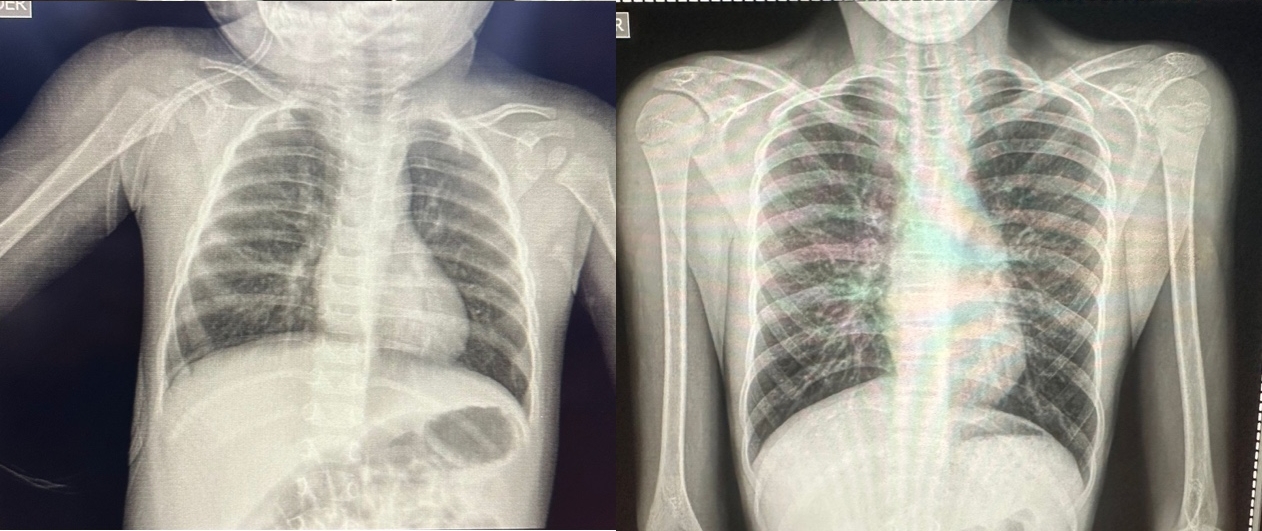

En nuestro hospital, ponemos a tu disposición una amplia gama de servicios de diagnóstico por imagen diseñados para ofrecer precisión y rapidez en la detección y monitoreo de tu salud. Contamos con tecnologías avanzadas y personal altamente capacitado para realizar tomografías, rayos X, ultrasonidos, mamografías y electrocardiogramas.